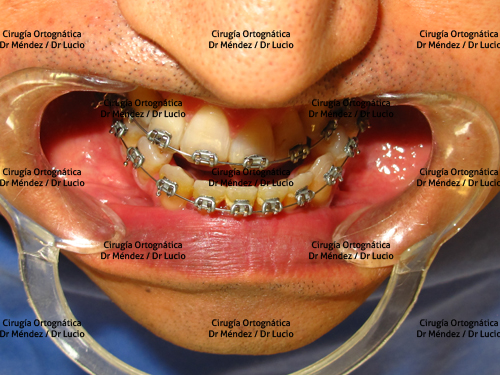

HIPOPLASIA MAXILAR Paciente operado de avance maxilar |

||